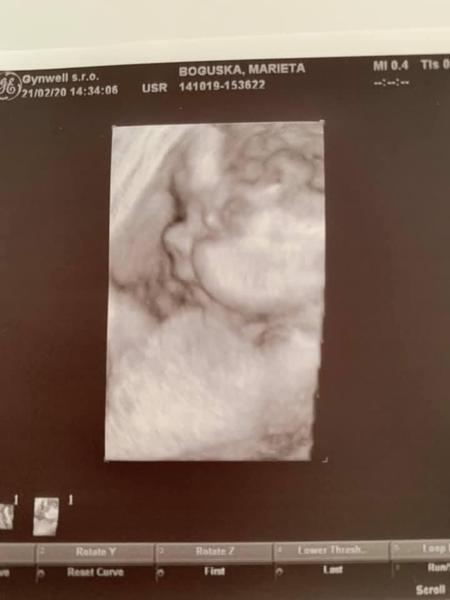

Velký nos na ultrazvuku. Máte zkušenost? A byl pak normální?

Ahoj, mám nevšední dotaz. Měli vaše miminka na fotkách z ultrazvuku velký nos a ve skutečnosti pak byl normální? Vím že mohou být ty ultrazvukové fotky zkreslené... Ano důležitější je, že je mimčo zdravé ❤️ jen mě to zajímá.

nam doktor rikal, ze pokud ma mlade na tom 3d ultrazvuku velkej nos, tak je to tim, ze pri snimani zaklonilo hlavu 🙂 ze maj jinak vsechny pidiknoflik

Mají často nos přimáčknutý, takže všelijaké patvary. Většina mimin má pidiknoflíčky pršáčky, konečný tvar se formuje po 3 letech.

Dcera měla na jednom utz místo nosu pěkný frňák a po narození po něm nebylo ani vidu. Má krásný nosík, tak se neboj. Utz muže zkreslovat ;)